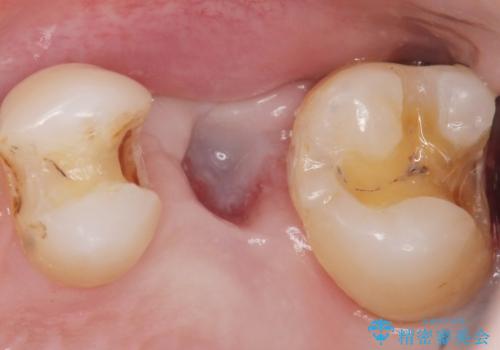

痛みやしみるなどの症状はありませんでしたが、銀の詰め物を除去したところう蝕を認めました。

インプラント埋入まで抜歯後(左上5)の骨の治癒を待つ間に、治療期間の短縮を図り先んじて両隣在歯(左上4,6)のインレー修復を行っております。